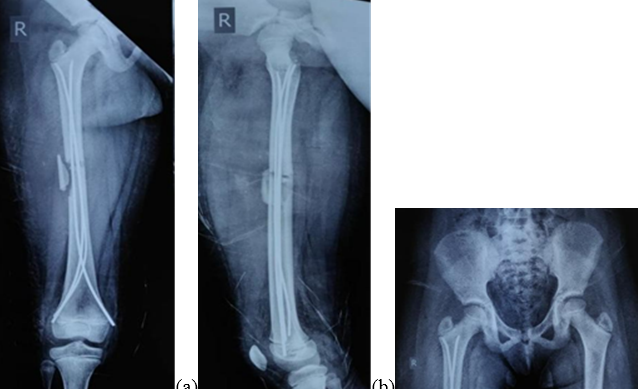

Figure 3: (a, b, c) Three months postoperatively (anteroposterior (AP), pelvis and both hips -AP and lateral).